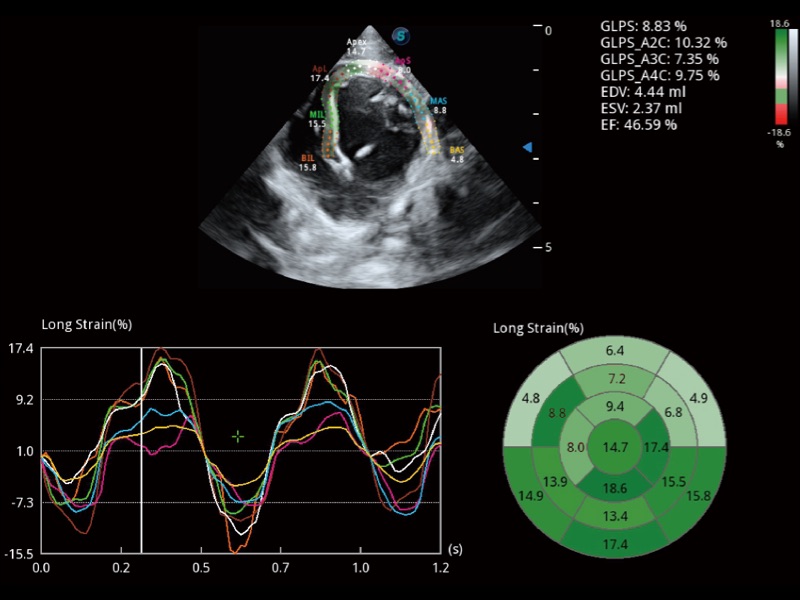

• Auto EF 心内膜自动描迹

能够基于左心室壁追踪和辛普森法,自动计算射血分数,支持多个可移动点描迹,与手动测量相比,极大节省了动物医生的时间和精力。